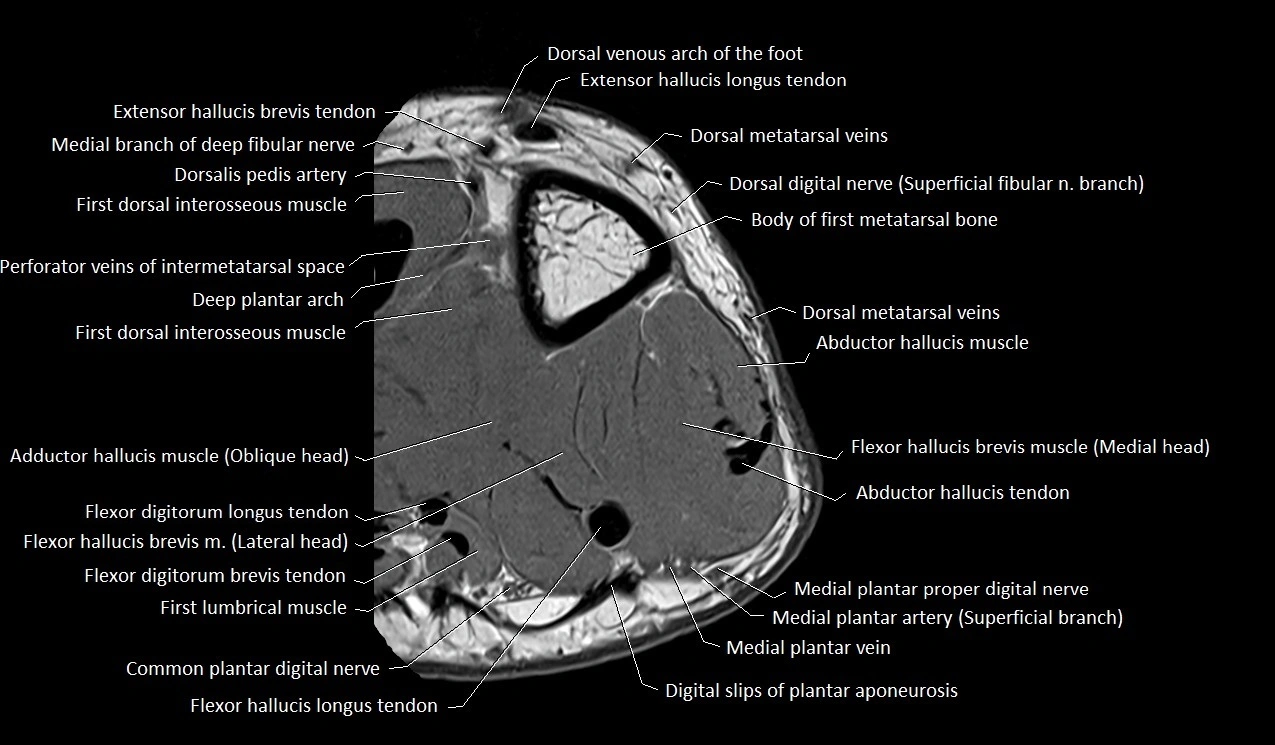

MRI image

image